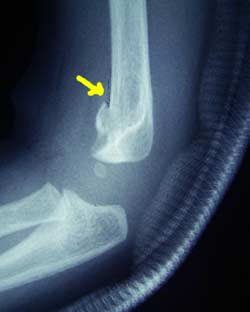

| 7月21日 骨折直後 矢印と矢印の間、線が見える。 子供の骨は軟らかいので、ボキッとおれず、若草を折ったようになるそう。 硬い割り箸との違いか。 |